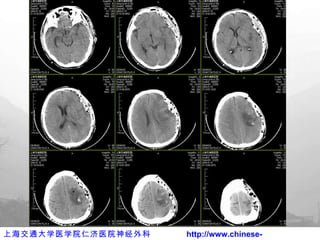

手术切口

术 中

术后亚低温治疗

亚低温治疗

术后 CT 复查